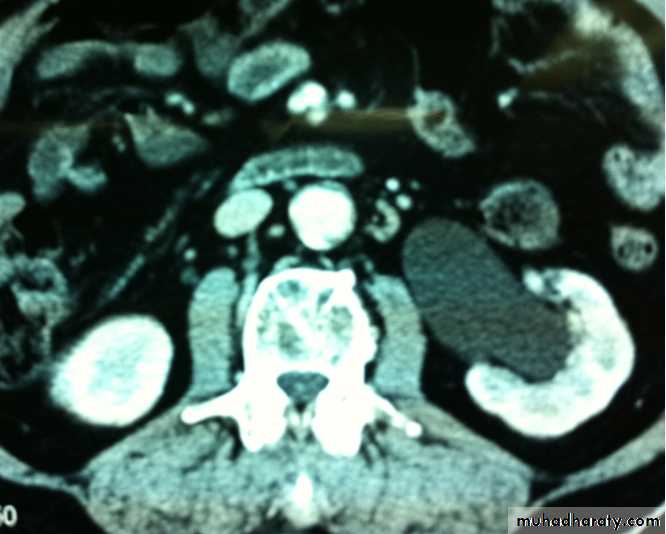

Ct enhanced

Big simple renal cyst(non enhancing mass homogenous) treatment is conservative or drainge if symptomaticWhat's the Diagnosis?

Renal cyst type 4 with calcification and peripheral enhancement needs radical nephrectomyBosniak's class II renal cysts. A, CT scan shows right renal cyst with thin internal septation.